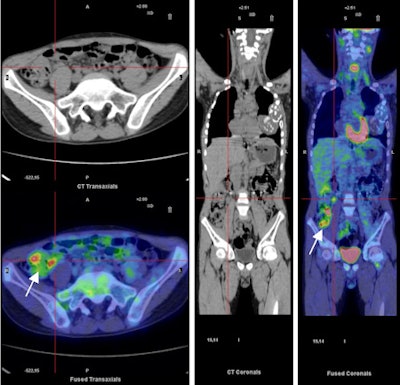

| F-18 FDG PET/CT images (trans-axial and coronal slides) in a patient with active Crohn's disease. Images show areas with increased glucose metabolism. A reactive lymphonode is detectable (defined by red lines) but it is not necessarily an infected site. The white arrow shows activity in the inflamed gut wall. Because of the lack of specificity of the radiopharmaceutical these areas can be inflamed or infected. A.W.J.M. Glaudemans, F. Maccioni, L. Mansi, R.A.J.O. Dierckx, A. Signore. Imaging of cell trafficking in Crohn's Disease. J. Cell. Physiol. 223: 562-571, 2010. |